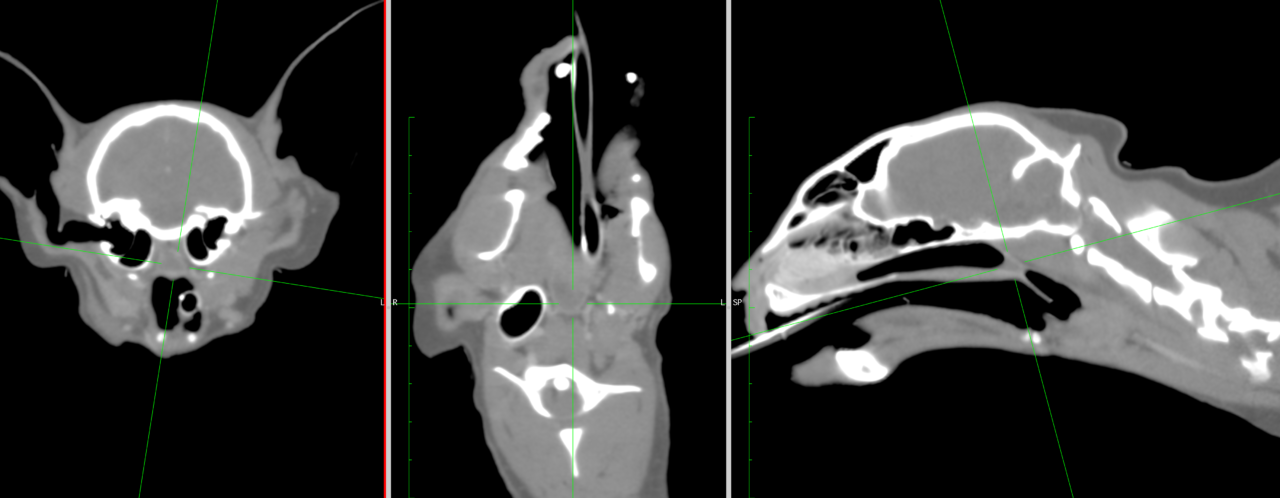

猫の鼻咽頭狭窄に対するバルーン拡張術

の鼻咽頭狭窄に対するバルーン拡張術(Balloon Dilation )は、非侵襲的な治療法としてよく利用される手法です。

鼻咽頭狭窄とは?鼻咽頭(鼻腔と咽頭の間の空間)が狭窄し、呼吸困難や慢性的なくしゃみ、鼻汁、いびき、喘鳴などを引き起こす疾患です。原因は先天性異常、慢性炎症(ウイルス性鼻気管炎や真菌感染症)、外傷、術後の瘢痕などが考えられます。

バルーン拡張術の概要は、バルーンカテーテルを用いて狭窄部を拡張し、通気を改善する治療法です。適応症例としては内科治療(抗炎症剤、抗生剤)で改善しない鼻咽頭狭窄です。エックス線透視装置を用いて、狭窄部位にバルーンを誘導し、拡張、一定時間(15分程度)保持します。※今回は7気圧で拡張